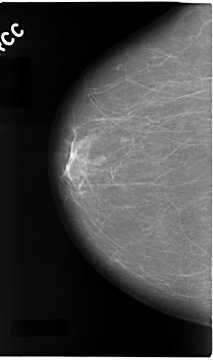

C_0079_1.RIGHT_CC

RIGHT_CC LINES 4680 PIXELS_PER_LINE 2768 BITS_PER_PIXEL 12 RESOLUTION 50 NON_OVERLAY